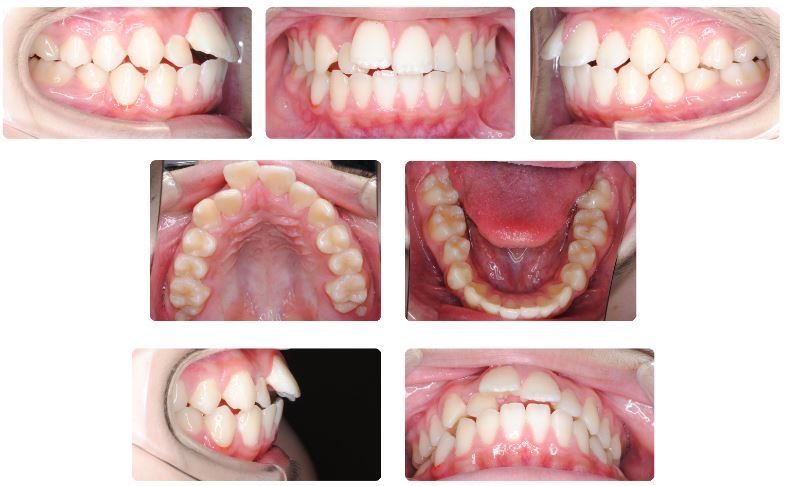

主訴:口が閉じにくい

初診時年齢:14歳

性別:男性

診断名:上下顎前突

抜歯/非抜歯:抜歯

装置名:マルチブラケット装置

上あごの前歯が出ていて口元の出具合が気になる、口が閉じられないことが主訴で来院されました。

特に上あごの前歯のサイズが大きめなうえ、下あごが相対的にやや前方に位置しており切端咬合状態でした。

口元が閉じにくいこと、特に上あご前歯のサイズが大きめであることから上下あご共に小臼歯抜歯による治療を選択、可能な限り前歯を奥に下げることで口を閉じやすい状態にすることを目的としました。